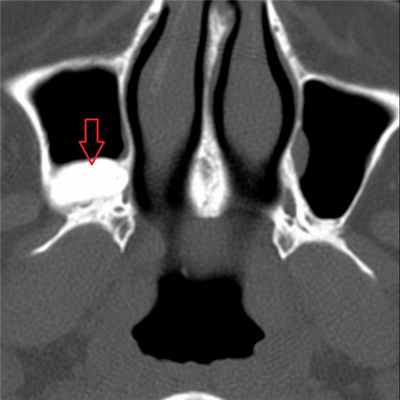

Ретенционные кисты формируются в результате обструкции выводных протоков желез слизистой оболочки [8]. При гистологическом исследовании ретенционные кисты имеют двустороннюю выстилку мерцательным цилиндрическим эпителием, стенка кисты состоит из соединительной ткани с наличием грубых коллагеновых волокон [9]. На спиральной КТ (СКТ) такие кисты имеют вид округлых гомогенных мягкотканных образований на широком основании, с четкими границами, без признаков разрушения кости, без связи с корнями зубов.

Установленные путем рентгенодиагностики кисты гайморовой пазухи всегда следует дифференцировать от верхнечелюстных кист одонтогенного типа, врастающих в пазуху, но фактически находящихся вне ее просвета.

Механизм внедрения одонтогенных кист в гайморову пазуху заключается в поднятии растущей кистой нижней стенки пазухи вместе со слизистой оболочкой, выстилающей эту стенку изнутри. Выпячиваясь в пазуху и истончаясь, эта стенка под давлением жидкого содержимого кисты приобретает полукруглую форму, и, таким образом, тень кисты на рентгенограмме становится неотличимой от описанных нами выше кист, исходящих из слизистой оболочки самой гайморовой пазухи.

Однако в ряде случаев такая одонтогенная киста может быть по снимку в подбородочноносовой проекции легко отличима от последних по характерному признаку резко выраженной полоски уплотнения в области верхнего полукруглого контура тени кисты. Описываемый симптом можно объяснить костной регенерацией приподнятой нижней стенки пазухи из надкостницы, прилегающей к кисте.